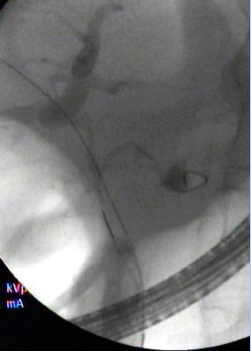

complex_ercp.jpg

Complex ERCP in a patient with bile duct cancer

• ERCP with stent placement to open a narrowed bile duct and improve quality of life in patients with advanced disease. This procedure must be performed by an advanced interventional endoscopist proficient in using this approach.

• ERCP guided by EUS to relieve obstructions in the bile ducts caused by cholangiocarcinoma, and to relieve jaundice in patients when the tumor cannot be removed.